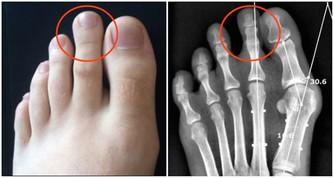

1932年的一項研究結果得出,改變飲食有助於改善蛀牙問題。研究人員得出結論,缺乏礦物質和脂溶性維生素以及過度攝取植酸與加工糖較易引起蛀牙。

植酸會阻擋形成健康牙齒結構的必要元素(如鈣)的吸收。植酸常在酒醅中被發現,如燕麥、麥片和餅乾。要防止蛀牙,應避免食用含有未發酵植酸的穀物。

礦物質是對抗蛀牙的關鍵。當牙齒琺瑯質變弱,就失去礦物質的含量。補充流失礦物質的最好辦法(除了食用富含礦物質的食物以外)就是使用礦化牙膏。這就是為什麼許多市售的牙膏都含有氟的成分,它能夠促進牙齒琺瑯的健康。